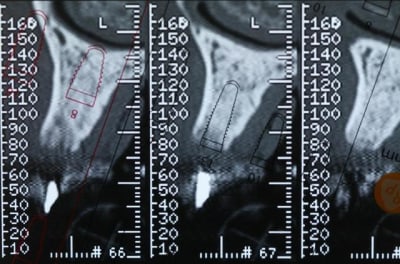

Bon voila le scann de 11-12 (pas 21-22 comme noté)

C'est vrai que j'ai à mort d'os en épaisseur.

Le manque est surtout en hauteur.

Dans tous les cas je refais 21 en même temps.

le montage guide RX laisse supposer un manque d'un mm en 12 et ok en 11. Surcomble en cj pour en éliminer au cas où avant les empreintes